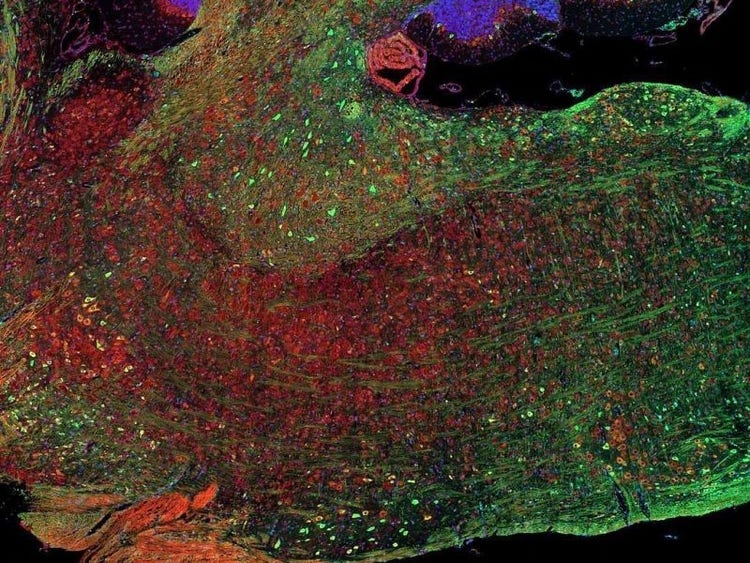

Fluorescence imaging of a mouse brain

尽管每幅图像近看各不相同,但将其拼接在一起则可组成一幅小鼠大脑的荧光图像。

英国科学家乔治·斯托克斯在用紫外线照射矿物萤石时首次观察到了矿物萤石发出的荧光,并创造了“荧光(fluorescence)”这个词。斯托克斯注意到荧光的波长比激发光的波长更长,这种现象现在被称为斯托克斯位移。无论是自然具有荧光的材料(称为原发荧光或自发荧光),亦或是经过有机染料处理后产生荧光的材料(称为次生荧光),荧光显微镜都是研究这些荧光发光材料的最佳工具。